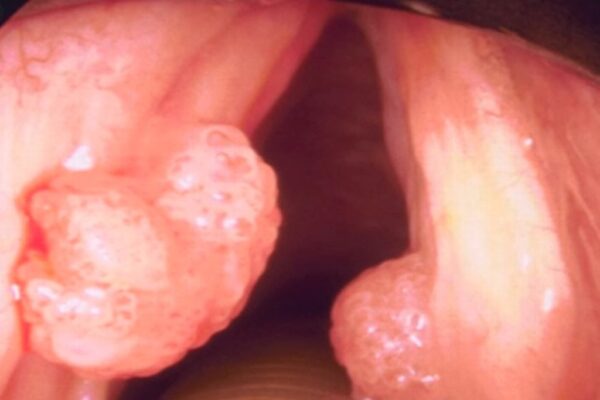

Parálisis de los pliegues vocales

La parálisis de los pliegues vocales puede ser consecuencia directa de una lesión o daño en el nervio vago o en el nervio laríngeo recurrente, dos importantes componentes del sistema…